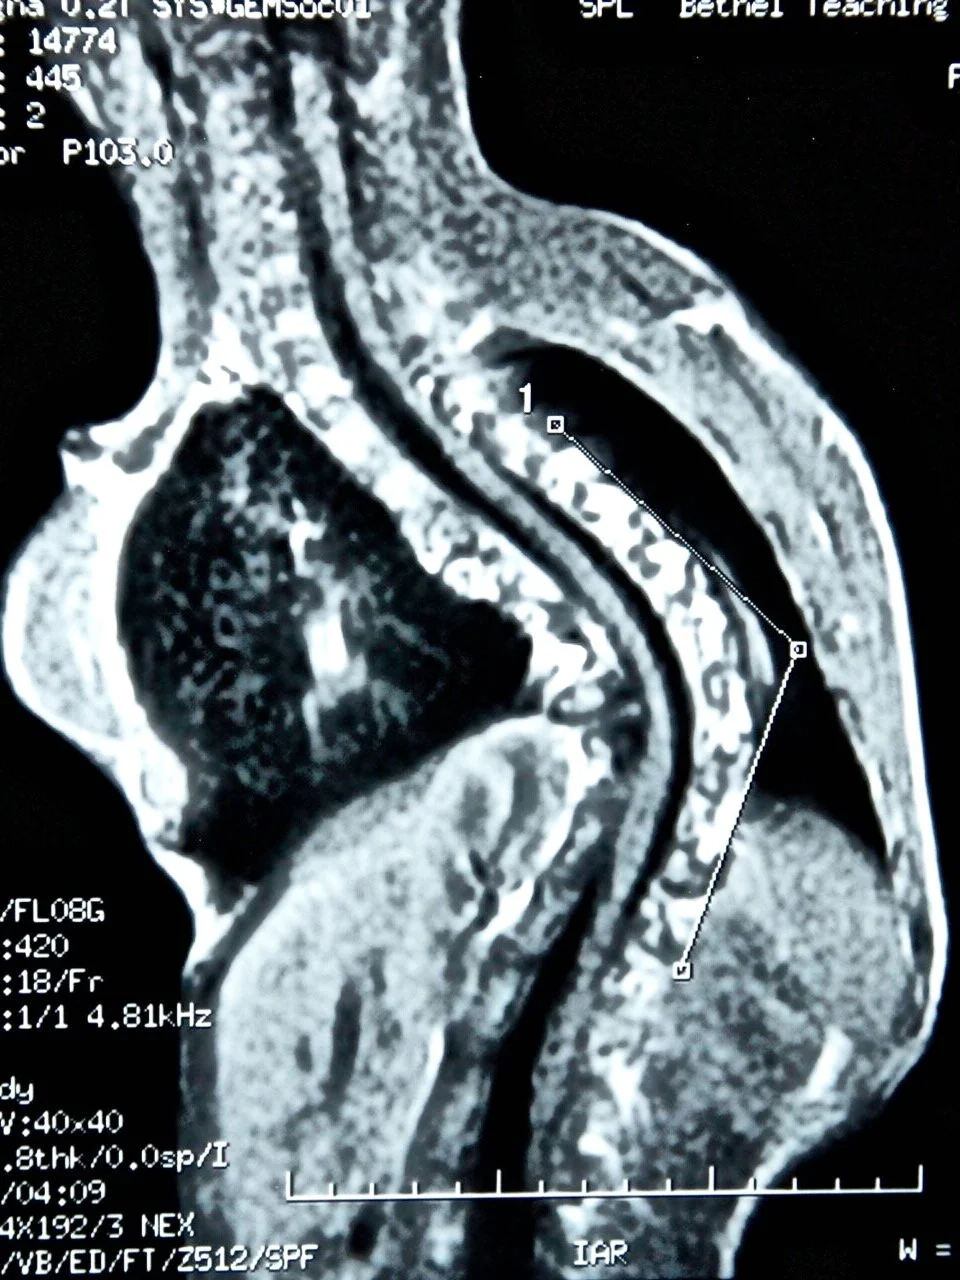

Ahmed’s moderate left scoliosis is complicated by spinal cord issues: he is developing a Chiari 1 malformation in which the lower part of the brain extends through the bottom of the skull. He also has a syrinx, a fluid-filled cavity inside the cord. This is complex, but treatable.